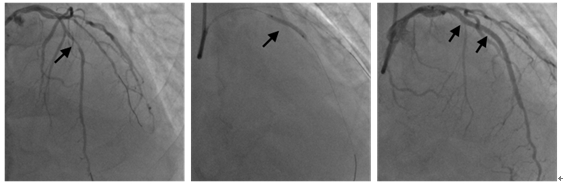

①右侧桡动脉入路,Pilot50导丝在SAL1.0 指引导管下,顺利通过RCA闭塞段到远端,对比剂注射后证实导丝在血管真腔远段(图2A)。②2.5mm×20mm 顺应性球囊扩张闭塞段,造影示闭塞后血管较大(图2B)。③于远段置入 2.5mm×36mmDES支架;2.5mm×15mm高压球囊扩张,造影支架贴壁良好(图2C)。④EBU3.5指引导管插入左冠开口,分别送入2根Runthrogh NS 导丝到LAD 远段和对角支(图3A)。⑤2.5mm×20mm 顺应性球囊扩张LAD 中段病变(图3B);⑥于LAD中远段、近段分别置入2.75mm×36mm;2.75mm×29mmDES支架;造影支架贴壁良好(图3C)。

图2 RCA远段闭塞支开通过程及支架后最后影像

图3 LAD近中段处理过程及支架后最后影像